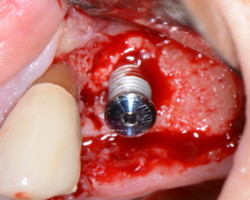

- Phase étiologique : Contrôler l’infection. Décontamination de la surface implantaire au moyen de l’aéropolisseur avec la buse pério + glycine.

Utilisation des inserts Implant Protect si débordement de ciment ou présence de tartre.

Décontamination à la Bétadine

Mise en place d’un gel antibiotique (Renvert europeen workshop 2008)